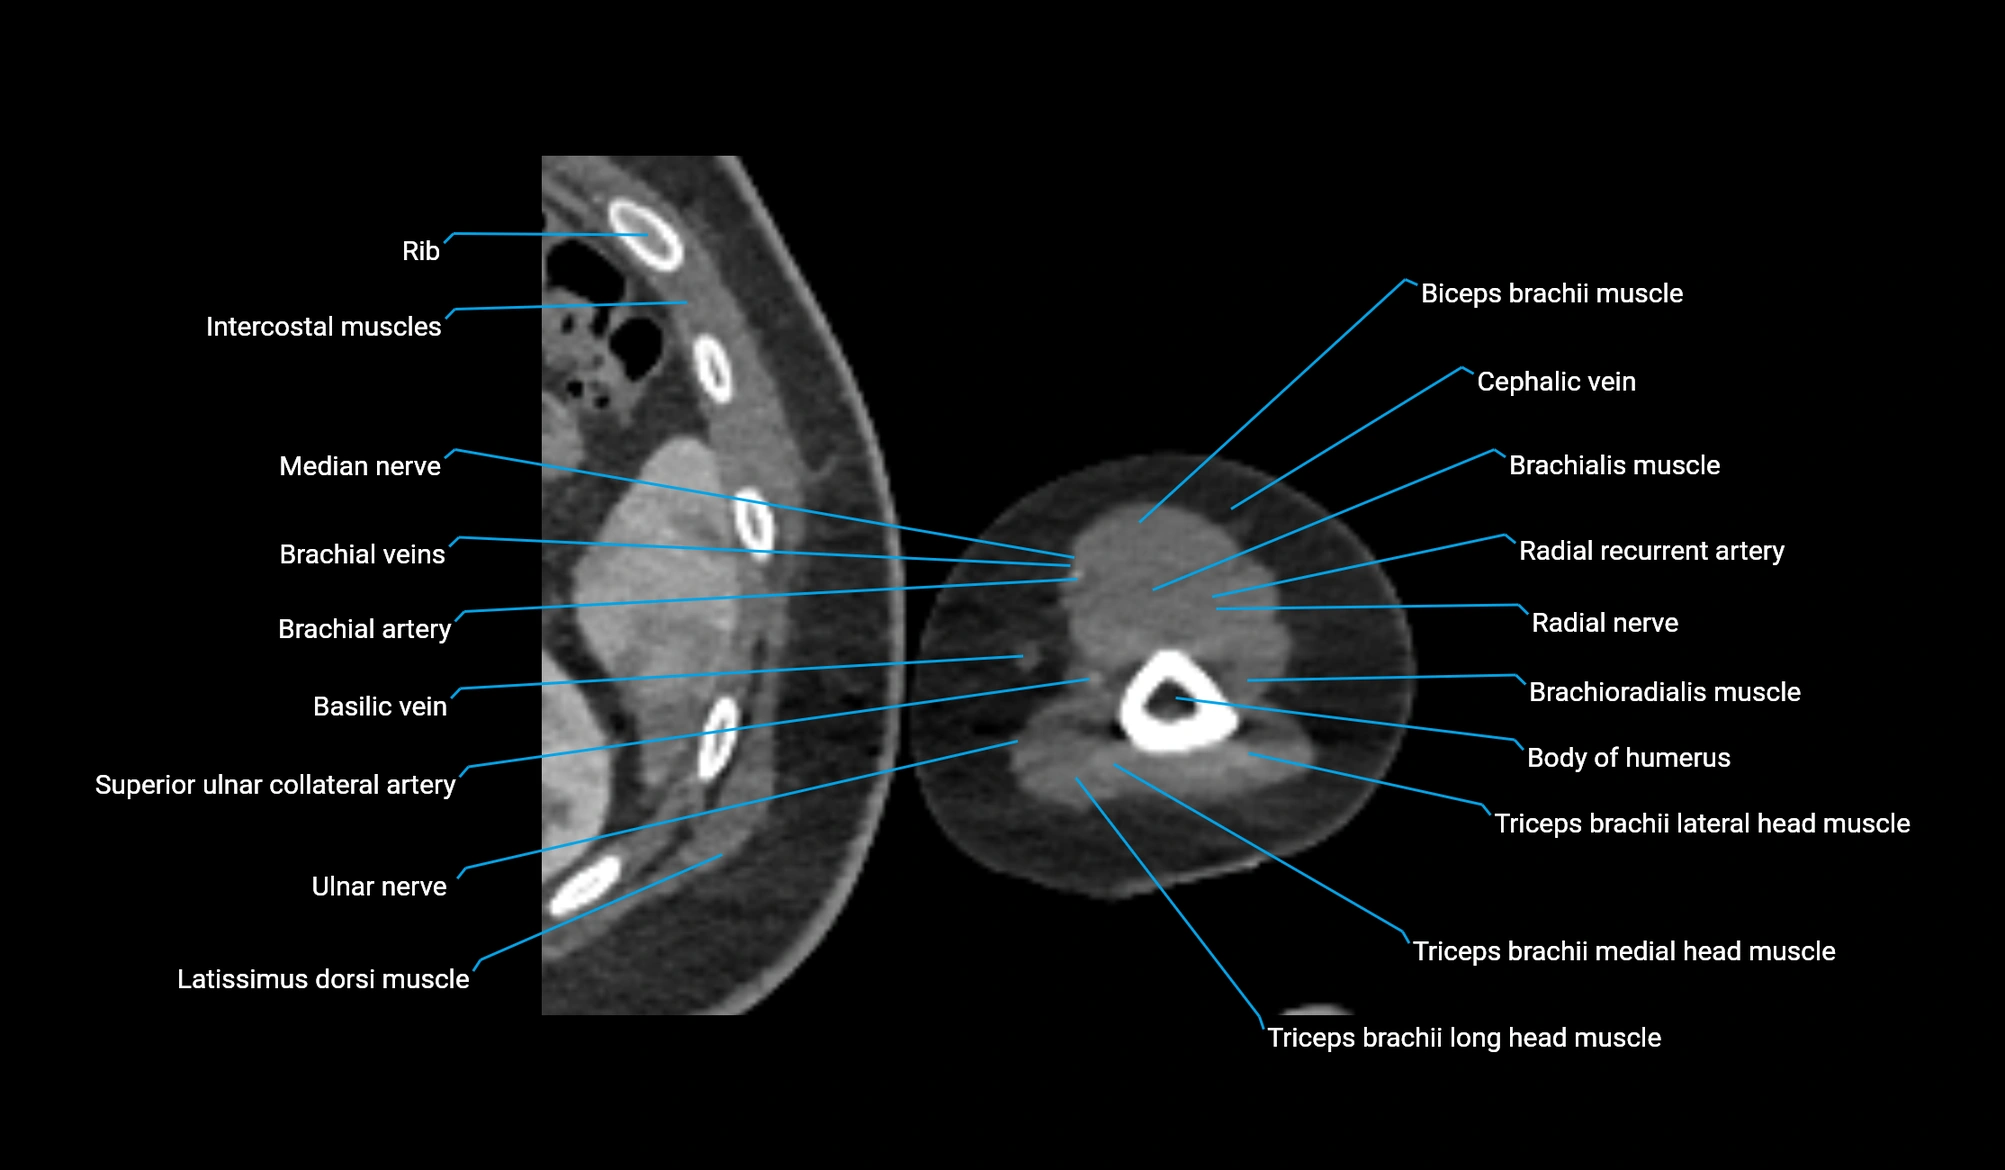

CT image